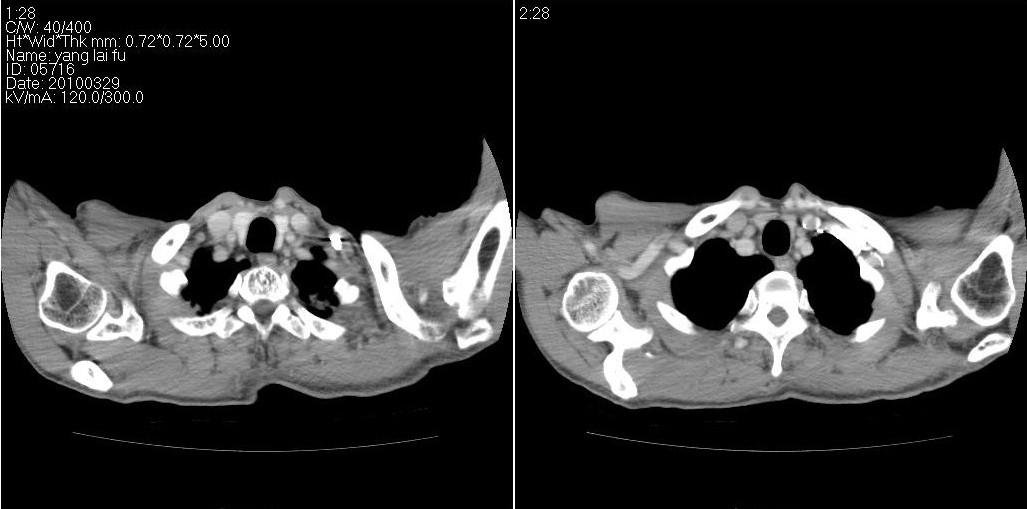

以下是ct检查的情况:

标题: ct增强: